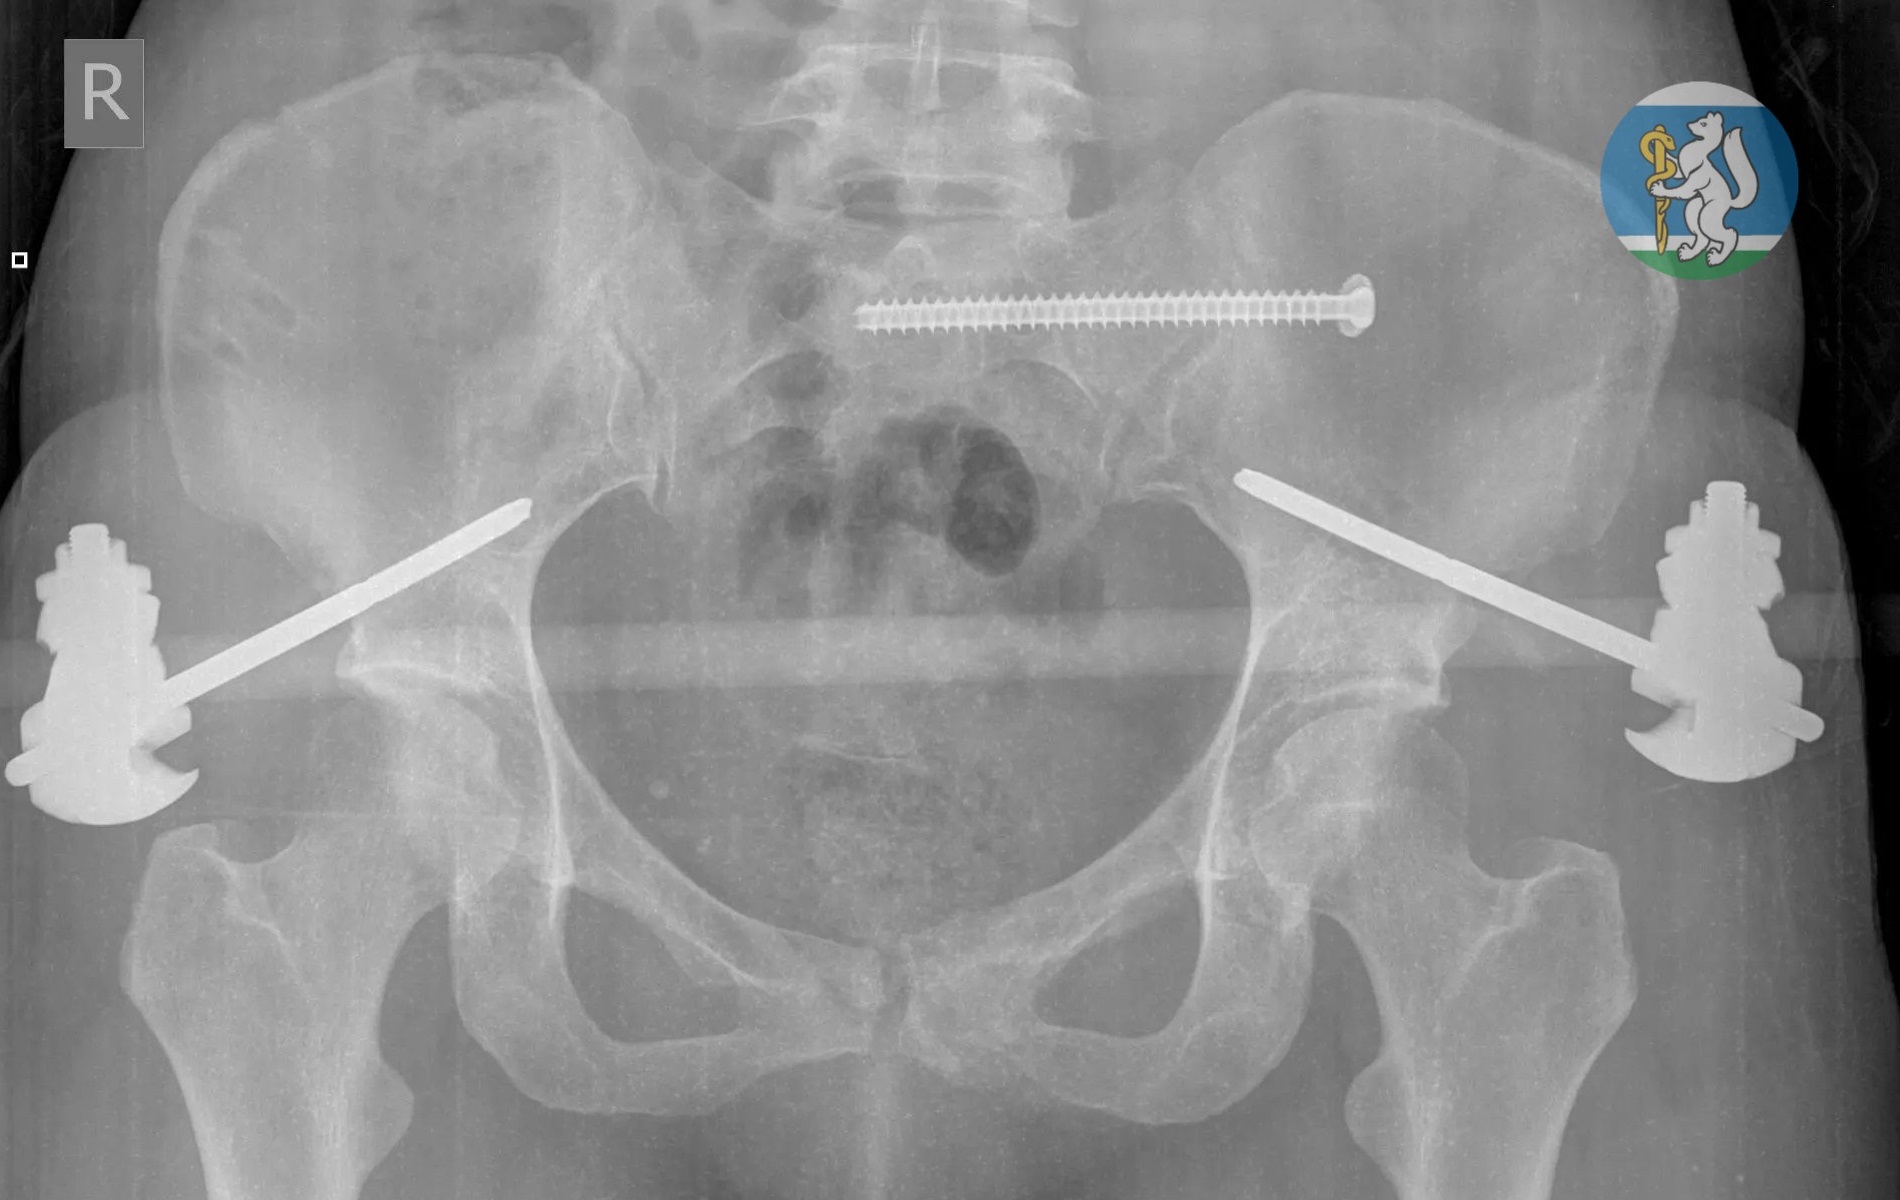

Когда бригада скорой помощи доставила упавшую с седьмого этажа свердловчанку в Городскую больницу №36 «Травматологическая», медики в результате обследования диагностировали у неё тяжелейшие повреждения: черепно-мозговую травму, повреждение шейного отдела позвоночника, множественные переломы костей таза, травму грудной клетки с повреждением лёгких, открытые оскольчатые переломы левой ноги. Большинство пострадавших с подобными травмами погибают ещё до приезда врачей.

Первоочередной задачей врачебной бригады в составе хирурга, травматолога, нейрохирурга и анестезиолога-реаниматолога было вывести пациентку из шокового состояния, зафиксировать переломы, остановить кровотечение. Несколько часов молодая женщина провела в операционной на грани жизни и смерти, но врачи смогли буквально совершить чудо.

После экстренной операции свердловчанка находилась в реанимации на искусственной вентиляции лёгких до полной стабилизации состояния. Через полторы недели её перевели в отделение травматологии, а ещё через две недели врачи успешно выполнили операцию по частичному демонтажу аппаратов внешней фиксации и синтезу сломанных костей.